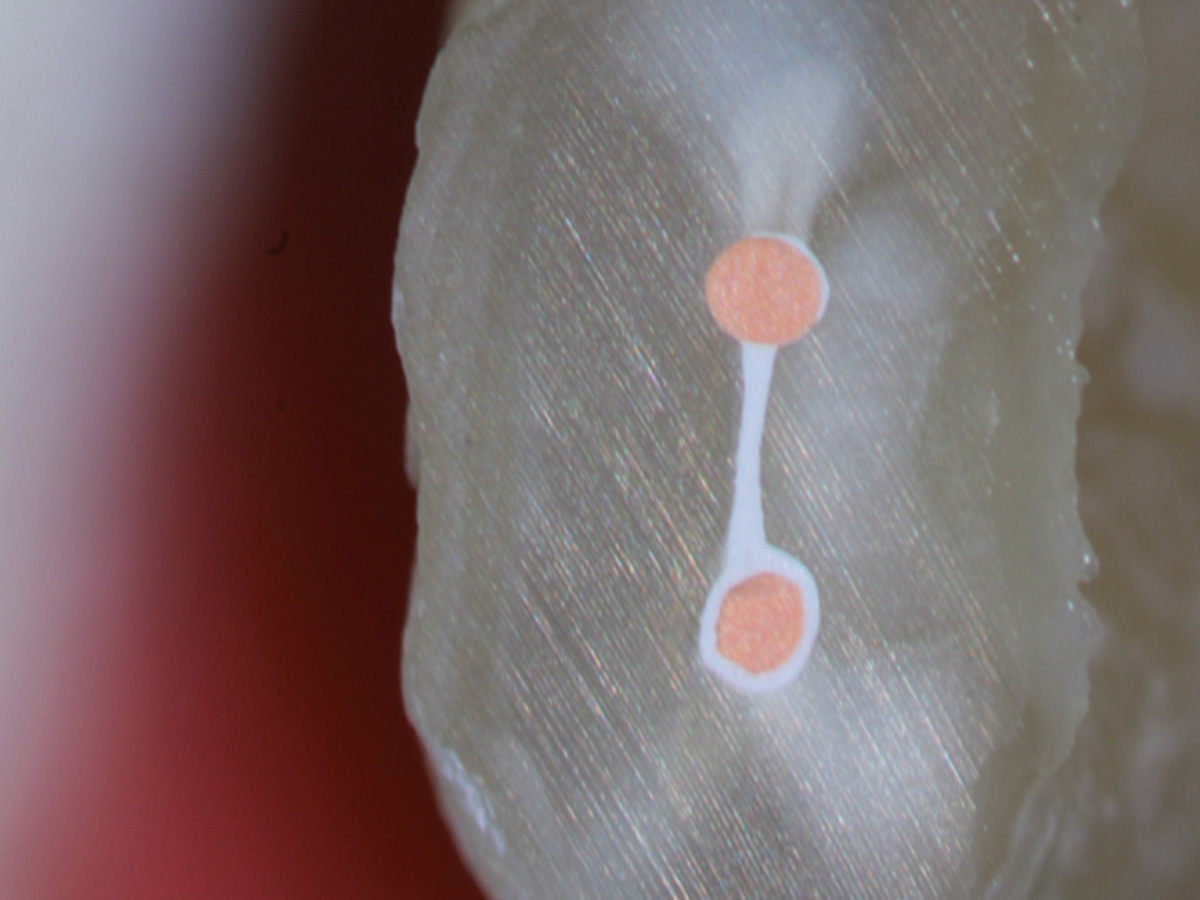

• Wurzelfüllung mit biokeramischem Sealer